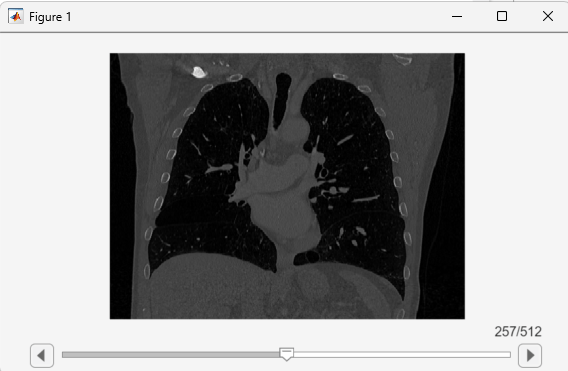

View the updated volume using sliceViewer, verifying that the window displays coronal slices.

sliceViewer(medVolReoriented)